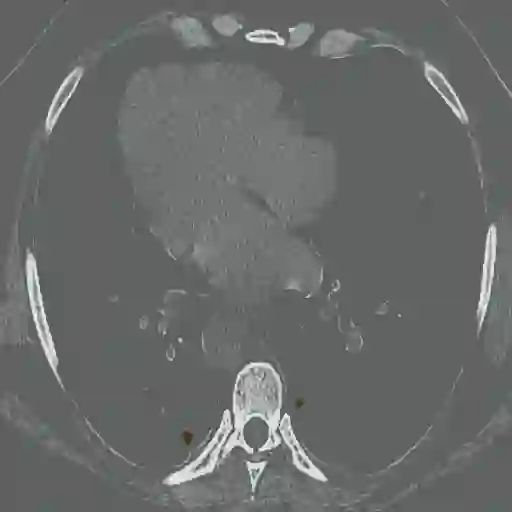

The novel coronavirus disease 2019 (COVID-19) has been spreading rapidly around the world and caused significant impact on the public health and economy. However, there is still lack of studies on effectively quantifying the lung infection caused by COVID-19. As a basic but challenging task of the diagnostic framework, segmentation plays a crucial role in accurate quantification of COVID-19 infection measured by computed tomography (CT) images. To this end, we proposed a novel deep learning algorithm for automated segmentation of multiple COVID-19 infection regions. Specifically, we use the Aggregated Residual Transformations to learn a robust and expressive feature representation and apply the soft attention mechanism to improve the capability of the model to distinguish a variety of symptoms of the COVID-19. With a public CT image dataset, we validate the efficacy of the proposed algorithm in comparison with other competing methods. Experimental results demonstrate the outstanding performance of our algorithm for automated segmentation of COVID-19 Chest CT images. Our study provides a promising deep leaning-based segmentation tool to lay a foundation to quantitative diagnosis of COVID-19 lung infection in CT images.

翻译:2019年新的冠状病毒疾病(COVID-19)在全世界迅速蔓延,对公共卫生和经济产生了重大影响;然而,对于有效量化COVID-19造成的肺感染,仍然缺乏研究;作为诊断框架的一项基本但具有挑战性的任务,分解在通过计算断层摄影(CT)图像测量的COVID-19感染的准确量化方面发挥着关键作用;为此,我们提出了对多个COVID-19感染区域进行自动分解的新型深层次学习算法。具体地说,我们利用综合残余变异学来学习一种稳健和直观的特征表征,并运用软关注机制来提高模型的能力,以区分COVID-19的症状。用公共CT图像数据集,我们验证了拟议的算法与其他相竞方法的功效。实验结果表明,我们自动分解COVID-19 Chest CT 图像的算法表现出色。我们的研究提供了一个充满希望的深度精细分解工具,为CT 图像中COVID-19肺感染的定量诊断奠定了基础。